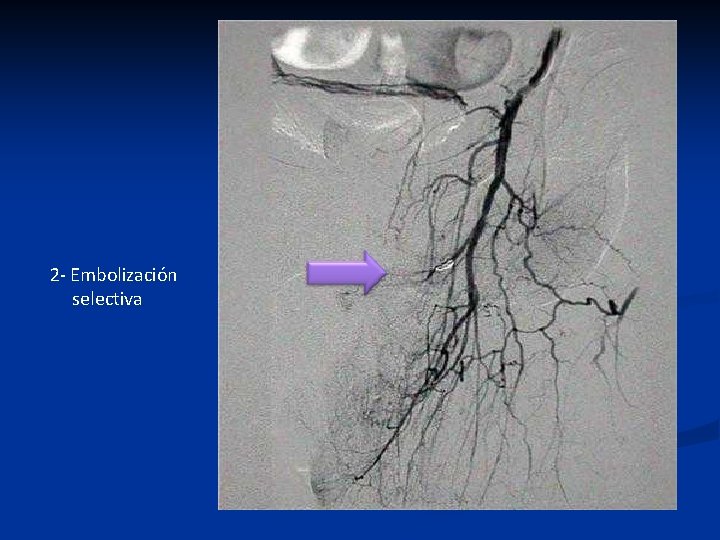

2 - Embolización selectiva